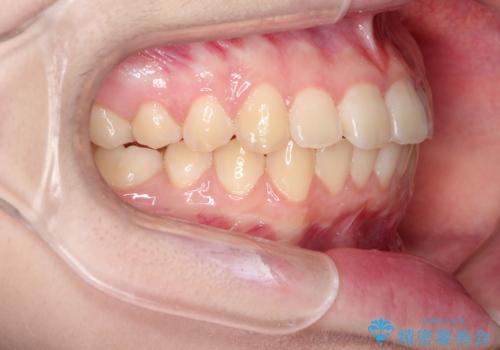

上下の前歯のガタガタを目立たず治したい インビザラインによる見えない矯正

受験生ということもあり、来院頻度が少ないマウスピース矯正で治療が終了できたことに満足いただけました。

上下の正中が一致していませんが、受験を控えているためご本人の希望もあり、いったん終了とさせていただきました。

治療の中断・再開が容易なのもインビザライン治療のメリットといえます。